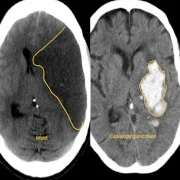

We specialize in neuro-trauma emergency care in Thane, providing immediate surgical interventions for patients suffering from severe head injuries, traumatic brain hemorrhages, skull fractures, and spinal cord injuries. Our dedicated neurotrauma emergency unit in Thane is equipped with 24×7 neurosurgical support, advanced ICU care, and rapid imaging facilities, ensuring that critical patients receive the fastest and most effective treatment possible.

– Traumatic Brain Injury